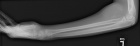

15 year old male seen c/o left elbow mass x5 years, significantly larger over 3 months

Zoom image: Radiological image Radiological image.